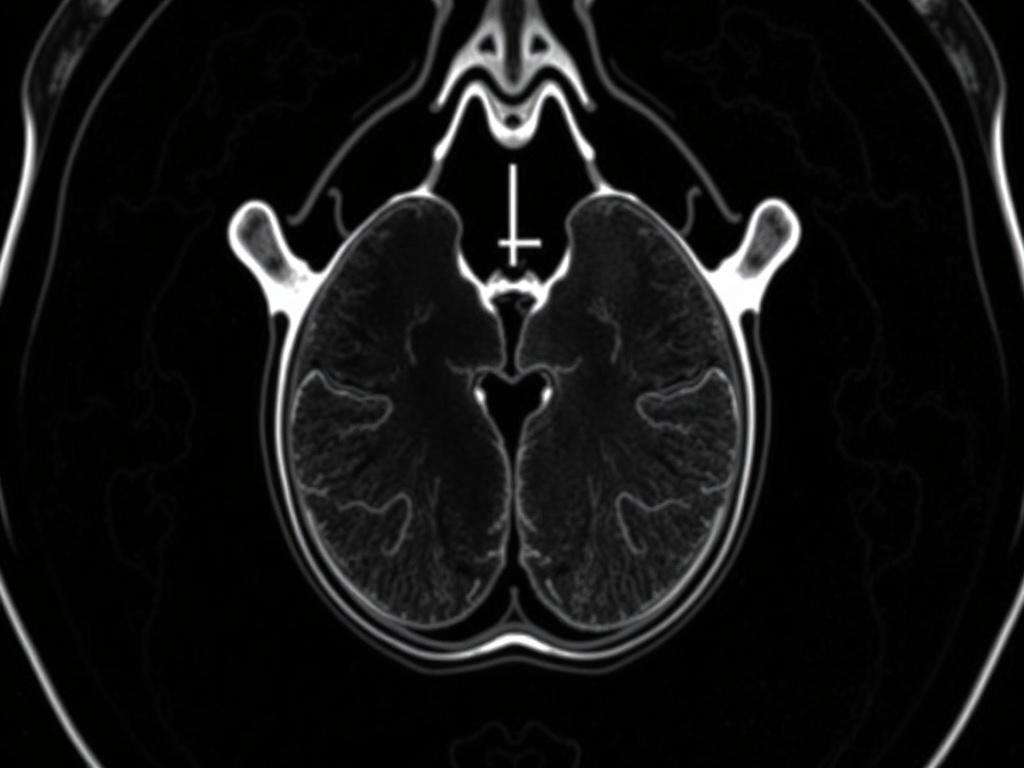

МРТ — метод исследования, который использует магнитное поле и радиоволны для создания подробных изображений внутренних структур организма. Для предстательной железы это означает возможность оценить её форму, размеры, структуру и наличие очагов, которые могут указывать на воспаление, опухоль или другие изменения. На сайте eurodicenter.ru можно получить больше информации про МРТ предстательной железы.

В отличие от УЗИ, МРТ даёт высококонтрастные снимки мягких тканей. Это особенно важно, когда нужно отличить доброкачественные процессы от подозрительных образований. Часто МРТ используют перед биопсией, чтобы прицельно взять материал из зоны с высокой вероятностью патологии.

Что показывает МРТ: конкретика без воды